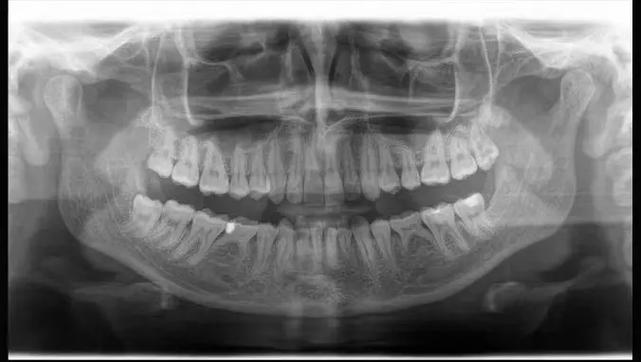

牙齿正畸的核心是通过施加持续、温和的生物力,引导牙齿在牙槽内缓慢移动,最终达到理想的位置和咬合关系,常见的牙齿问题包括龋齿、龅牙、地包天、牙齿拥挤、牙缝过大等,这些问题不仅影响外观,还可能导致牙周病、颞下颌关节紊乱等健康问题,牙齿拥挤不易清洁,容易积累食物残渣和细菌,增加龋齿和牙周炎的风险;咬合异常则可能引发咀嚼效率下降、面部肌肉疲劳等问题,正畸治疗能够通过排齐牙齿、调整咬合,从根本上解决这些隐患。

牙齿正畸的方式多样,患者可根据自身需求和经济条件选择,传统金属托槽矫正性价比高,适用范围广,但美观度稍差;陶瓷托槽颜色接近牙齿,兼顾美观与强度,适合对美观有一定要求的人群;自锁托槽摩擦力小,可缩短治疗时间,复诊间隔延长,适合学生或工作繁忙的群体;隐形矫正则通过透明牙套实现,几乎不影响美观,可自行摘戴,口腔清洁方便,但价格较高,对患者的依从性要求也较高,不同矫正方式的特点对比如下: